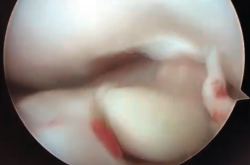

Figura 9. Cíclope, tejido fibroso interpuesto en la cara anterior de la plastia y que produce pinzamiento de la misma en extensión de rodilla.

Las limitaciones pueden ser tanto en flexión como en extensión, siendo las segundas mucho más limitantes funcionalmente. Mientras la disminución de la flexión suele ser fácil de recuperar mediante artrolisis artroscópica y manipulación bajo sedación, una disminución de 5 y 10° de extensión puede desembocar en una incapacidad importante con cojera de la marcha.